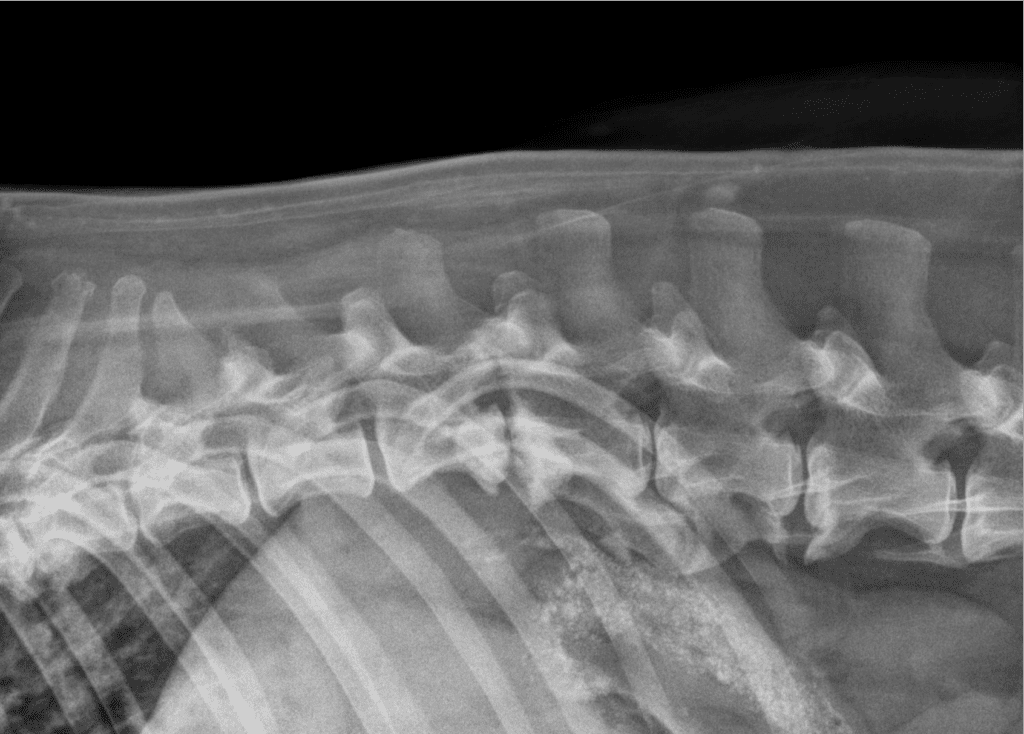

Teleradiology

Teleradiology Services

Our board-certified veterinary radiologist will assist with interpretation of all of the following imaging modalities:

• Radiographs